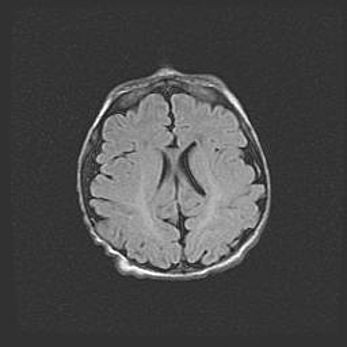

Множественные кисты обоих полушарий головного мозга, наибольшая из них в правой затылочной области. Ассиметричная атрофическая гидроцефалия.

Возраст: 7 месяцев

Вес: 5660 г

Пол: мужской

Окружность головы: 41,5 см

Срок гестации: 28-29 недель

Кисты головного мозга развиваются в результате многоочаговых некрозов вещества мозга и возникают вследствие перенесенной перинатальной инфекции, менингитов, энцефалитов, асфиксии, родовой травмы, расстройств мозгового кровообращения различного генеза. Образованию кист в веществе головного мозга плодов и новорожденных способствуют такие факторы, как высокое содержание в нем воды, недостаточная (или отсутствие) миелинизация и слабая астроглиальная реакция на повреждение.

Кисты могут сочетаться с гидроцефалией и другими поражениями головного мозга.